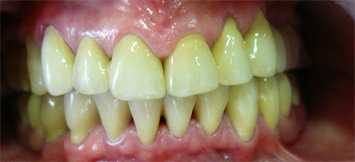

prije